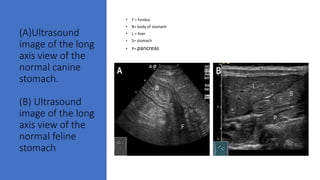

(A)Ultrasound

image of the long

axis view of the

normal canine

stomach.

(B) Ultrasound

normal feline

stomach

• F = fundus

• B= body of stomach

• L = liver

• S= stomach

• P= pancreas

(A)Ultrasound image of thelong axis view of the normal canine stomach. (B) Ultrasound image of the long axis view of the normal feline stomach • F = fundus • B= body of stomach • L = liver • S= stomach • P= pancreas